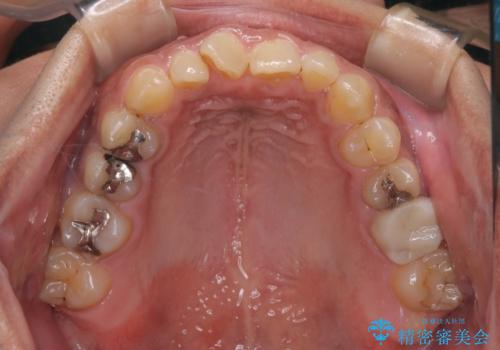

【モニター】インビザライン 前歯の捻れを治したい

- 30代男性

- 矯正装置

- インビザライン

- 上下の前歯のがたつきを主訴に来院されました。インビザラインで治療可能と判断致しましたので、IPR(歯と歯の間を削る処置)と歯列弓拡大をして

がたつきをとる治療計画を立てました。

マウスピースをしっかり使用していただいたことで、主訴である前歯のがたつきも改善され

リファイメントも1回のみで治療を終了することが出来ました。